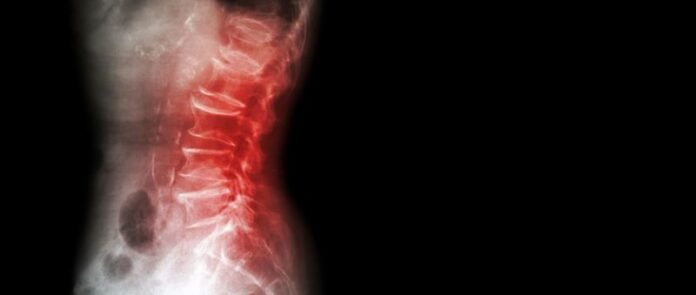

A spinal infection is a rare condition that develops when bacteria, fungi or viruses make their way into the spinal column. In most instances, spinal infections are classified further based on the specific location where the infection develops. Below, we take a closer look at the three most common classifications of spinal infections.

When bacteria or a virus ends up in your bloodstream and leads to the onset of an infection in your spine, it typically leads to one of these three types of infections:

- Intervertebral Osteomyelitis – This type of spinal infection affects the vertebrae and the adjacent vertebral disc. It is a serious type of infection that can present with fever, pain, chills, and neurological impairment leading to numbness or weakness in the extremities. If antibiotics can’t resolve the infection, a surgical procedure to remove the infected tissue and stabilize the spine may be required.

- Discitis – Patients with discitis will be dealing with an infection of their spinal discs, the spongy cushion that rests between vertebral segments. Pain, fever, tenderness, fatigue and stiffness in the spine typically accompany a spinal disc infection. Antibiotics can usually take care of discitis, but similar to intervertebral osteomyelitis, if the infection persists, a minimally invasive procedure to remove the disc and replace it with artificial hardware or a bone graft may be required.

- Epidural Abscess – An epidural abscess is an infection that develops within the epidural space, which is the area between the spinal cord and the vertebral canal. It is similar to other spinal infections in that it presents with pain, fever, fatigue and tenderness at the infection site, and it tends to respond well to antibiotics. In more severe cases, surgery to drain the abscess and relieve pressure may be performed, as can a more invasive procedure to remove the infected tissue.